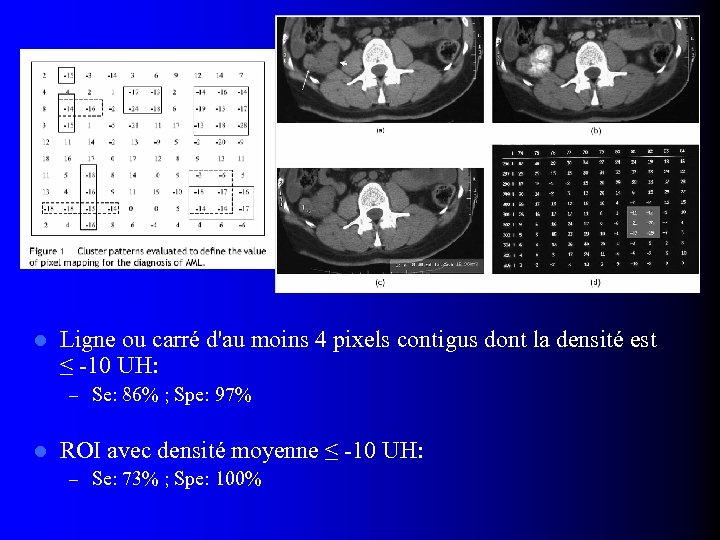

l Ligne ou carré d'au moins 4 pixels contigus dont la densité est ≤ -10 UH: – Se: 86% ; Spe: 97% l ROI avec densité moyenne ≤ -10 UH: – Se: 73% ; Spe: 100%

l Ligne ou carré d'au moins 4 pixels contigus dont la densité est ≤ -10 UH: – Se: 86% ; Spe: 97% l ROI avec densité moyenne ≤ -10 UH: – Se: 73% ; Spe: 100%

TDM: Profil de rehaussement l Rehaussement homogène – 79% - 100% des AML sans graisse l Non spécifique: – Carcinomes tubulo-papillaires et chromophobes – Surtout si petite taille (< 30 mm) (1) Jinzaki M et al, Radiology 1997; 205: 497 (2) Kim JK et al, Radiology 2004; 230: 677 (3) Kim JK et al, AJR 2002; 178: 1499

TDM: Profil de rehaussement l Rehaussement homogène – 79% - 100% des AML sans graisse l Non spécifique: – Carcinomes tubulo-papillaires et chromophobes – Surtout si petite taille (< 30 mm) (1) Jinzaki M et al, Radiology 1997; 205: 497 (2) Kim JK et al, Radiology 2004; 230: 677 (3) Kim JK et al, AJR 2002; 178: 1499